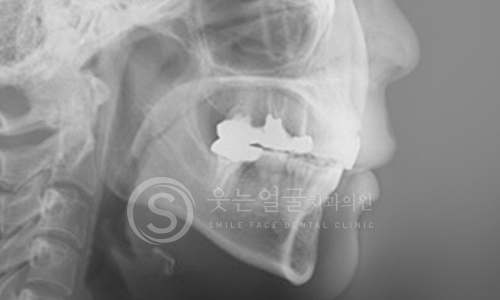

한눈에 보는

임플란트 전후사진